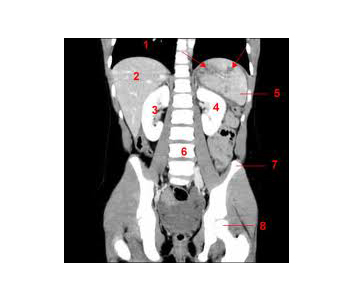

Le scanner utilise les rayons X et à l’intérieur du statif, il existe de part et d’autre de la table d’examen un tube à rayon X et un récepteur (barrette) qui tournent autour de la partie du corps à examiner; Pour chaque image, vous entendez le bruit de cette rotation.

Le mince pinceau de rayon X permet d’effectuer des coupes avec une dose très faible, qui apparaissent sur un écran de télévision après avoir été reconstruites dans un ordinateur.